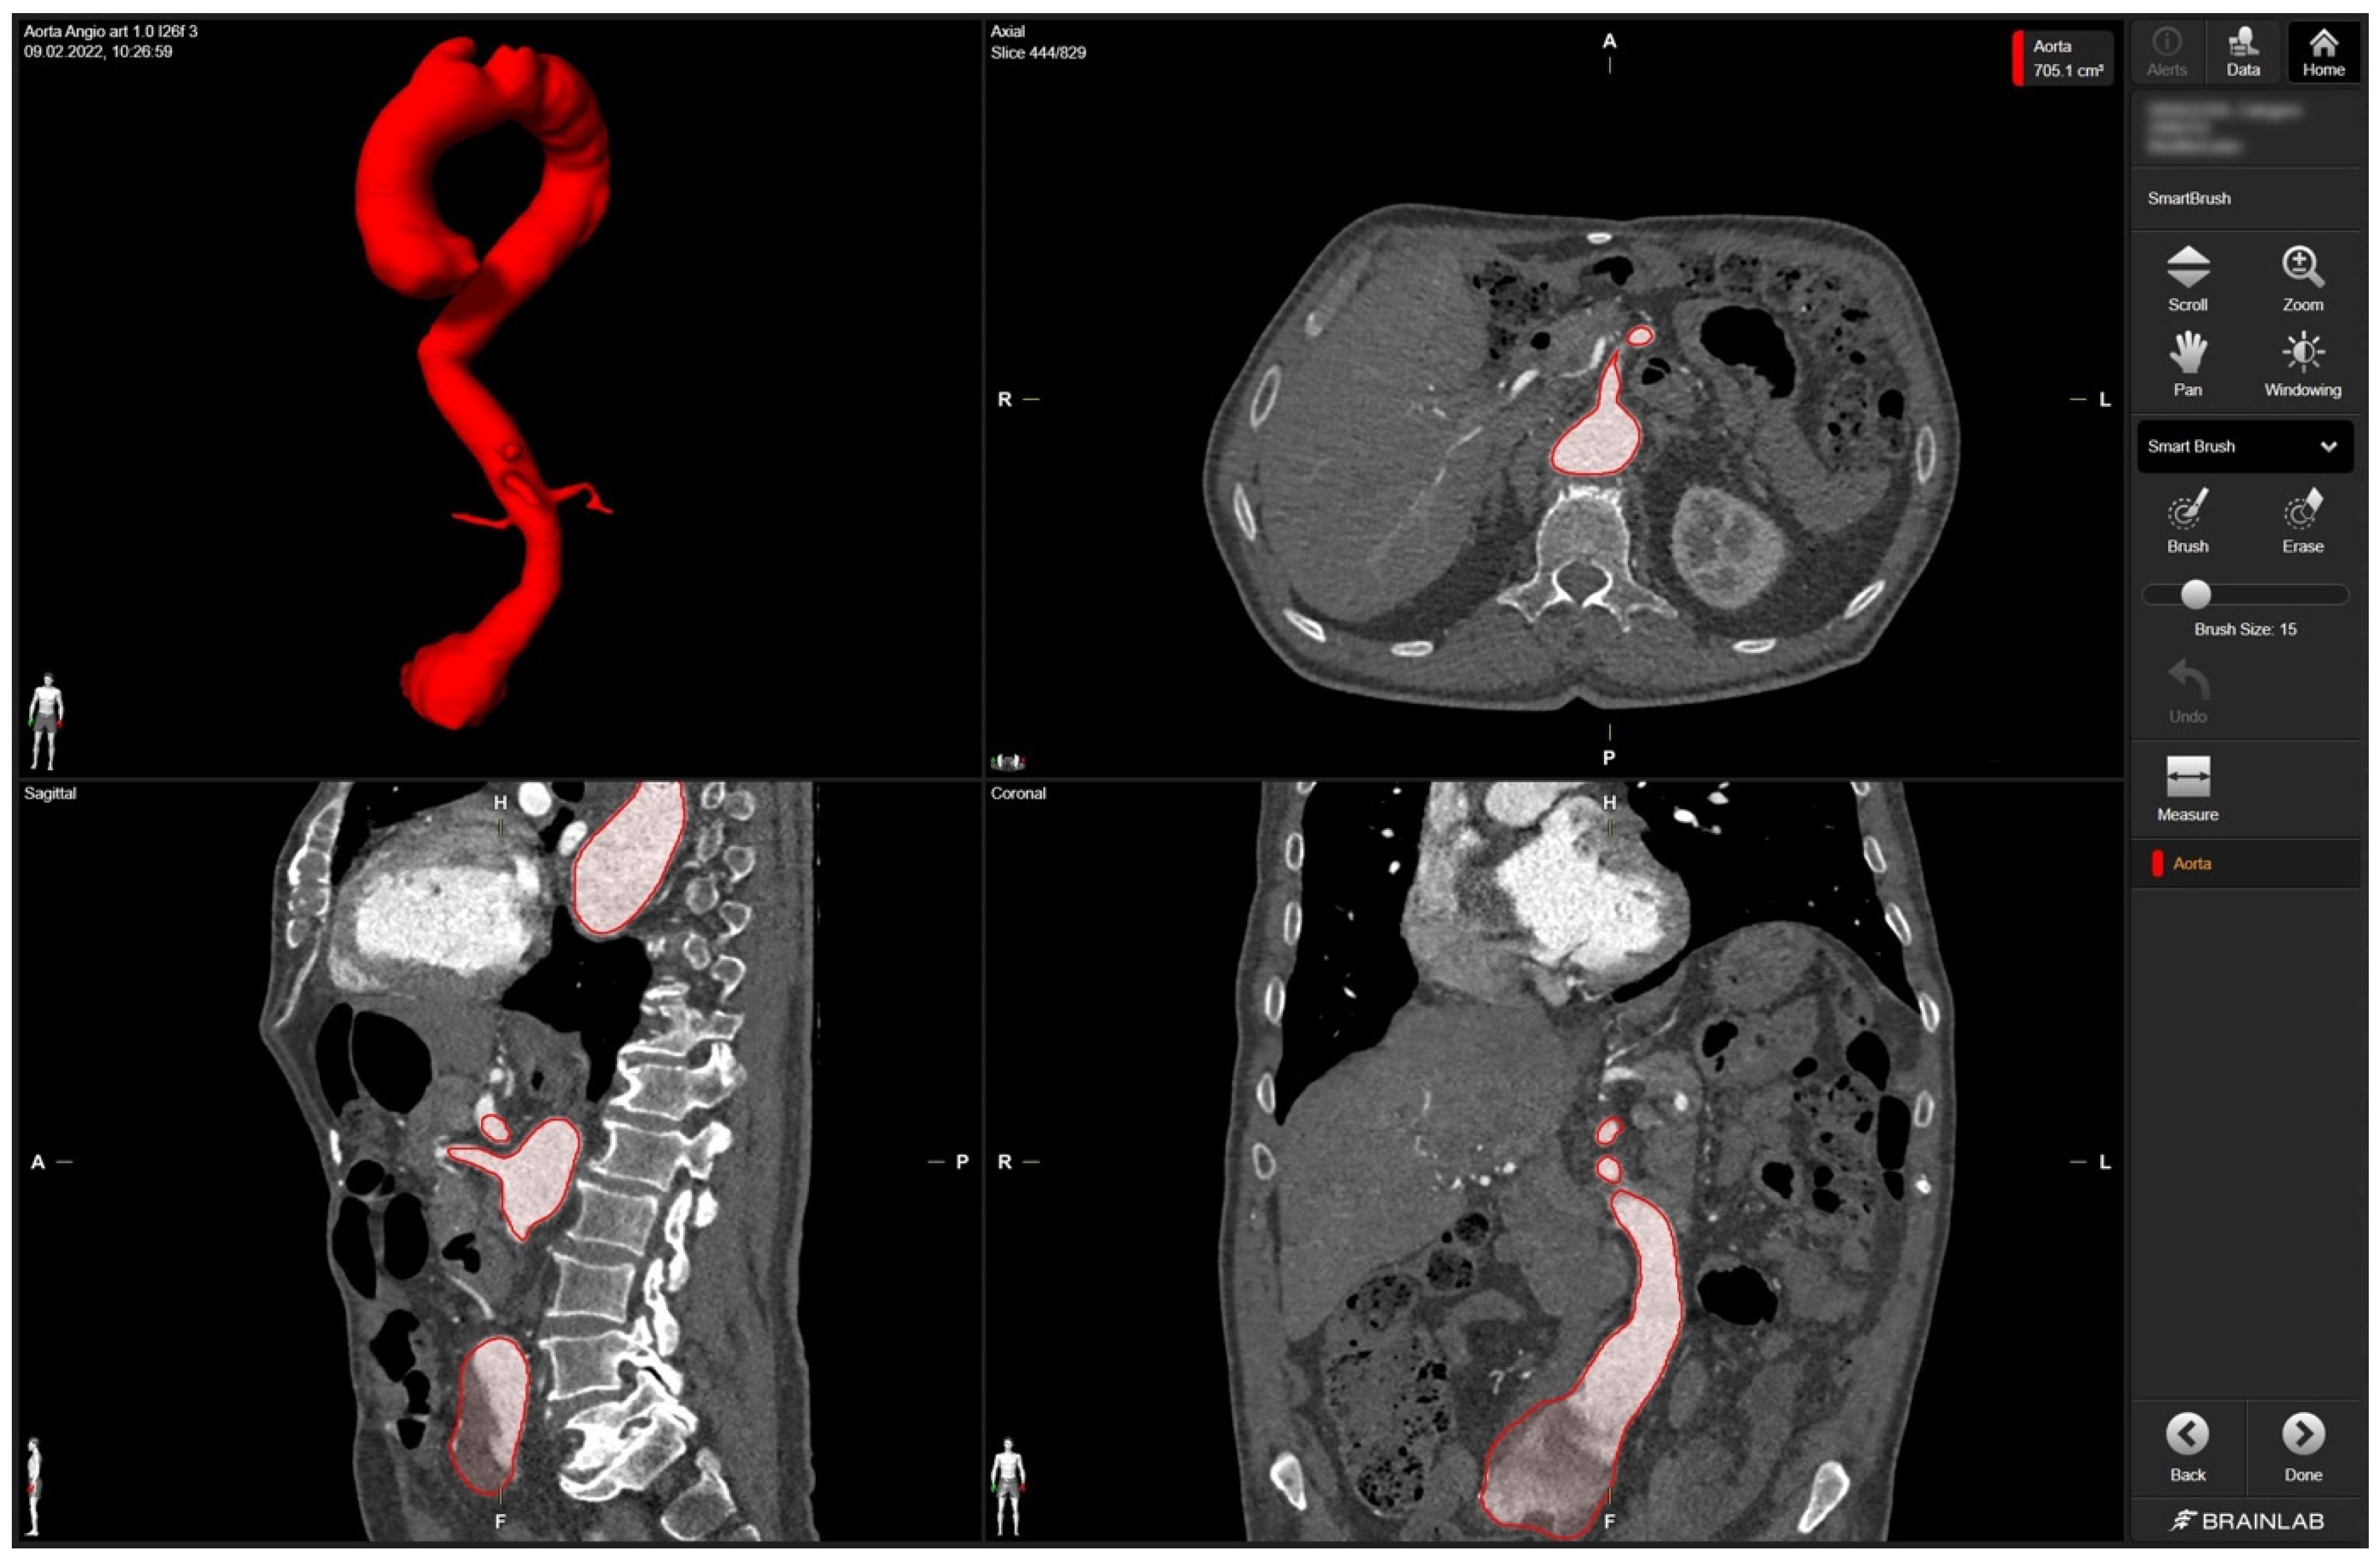

In detail, radiologic data sets for the patient’s thoracic and abdominal regions (soft-tissue window with contrast medium at arterial phase, axial sections, 1-mm slice thickness) were exported from the hospital‘s PACS server in DICOM format. The data set was imported into Brainlab Elements (backbone release 1.5.0.208, Brainlab AG, Munich, Germany). After aligning the data set, segmentation was performed using the “smart brush” software tool. This tool allows semi-automatic, three-dimensional object segmentation, which is conducted after manual segmentation of the desired object in two perpendicular planes; the result is calculated within seconds and can be reviewed and edited by the observer to ensure faultless segmentation without cutouts, especially near the vascular wall. Segmentation of the complete aorta (ascending portion, arch, descending portion including juxtarenal aortic aneurysm) including the proximal few centimeters of the main abdominal branches (celiac trunk, superior mesenteric artery, right and left renal arteries) could be conducted following the contrasted inner vascular lumen (Figure 1).

Figure 1. Screenshot of 3D aortic model after the segmentation process in Brainlab Elements (backbone release 1.5.0.208) using the “smart brush” tool. Upper left corner—fully sequenced aorta highlighted in red. In the upper right corner—axial view of the aorta marked in red with the mesenteric artery. In the lower left corner—sagittal view of the aorta with the initial portion of the mesenteric artery and part of the celiac trunk marked in red. In the lower right corner—coronary view of the aorta with the aortic segments IV and V marked in red.